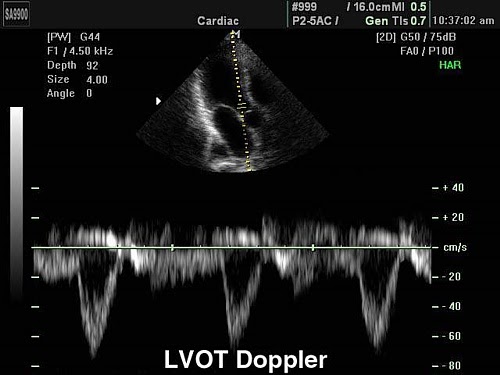

Режимы УЗИ на основе эффекта Допплера

PW - импульсно-волновой допплер. Данный режим позволяют оценить отдельные зоны по глубине. Используется для обеспечения анализа потока в конкретных объектах внутри исследуемого сосуда.

HPRF - допплер с высокой частотой повторения импульсов. Позволяет использовать высокую PRF на значительной глубине.

CW - постоянно-волновой допплер. С его помощью можно исследовать высокоскоростные потоки в области стенозов артерий, артериовенозных шунтов, также его применяют при исследованиях сердца.

Дуплексные и триплексные режимы (B+Color+D)

Дуплексный режим позволяет выявлять патологии каналов, нарушение их функций.

На его основе можно сделать вывод о строении вен и артерий, степени их сужения, выявлять патологии в строении сосудистой системы, поставить точный диагноз.

Триплексный режим расширяет возможности дуплексного. Добавляет режимы цветного допплера, по которым можно наглядно судить о направлении кровотока и его скорости, Также позволяет более точно оценить проходимость сосудов и степень стеноза.